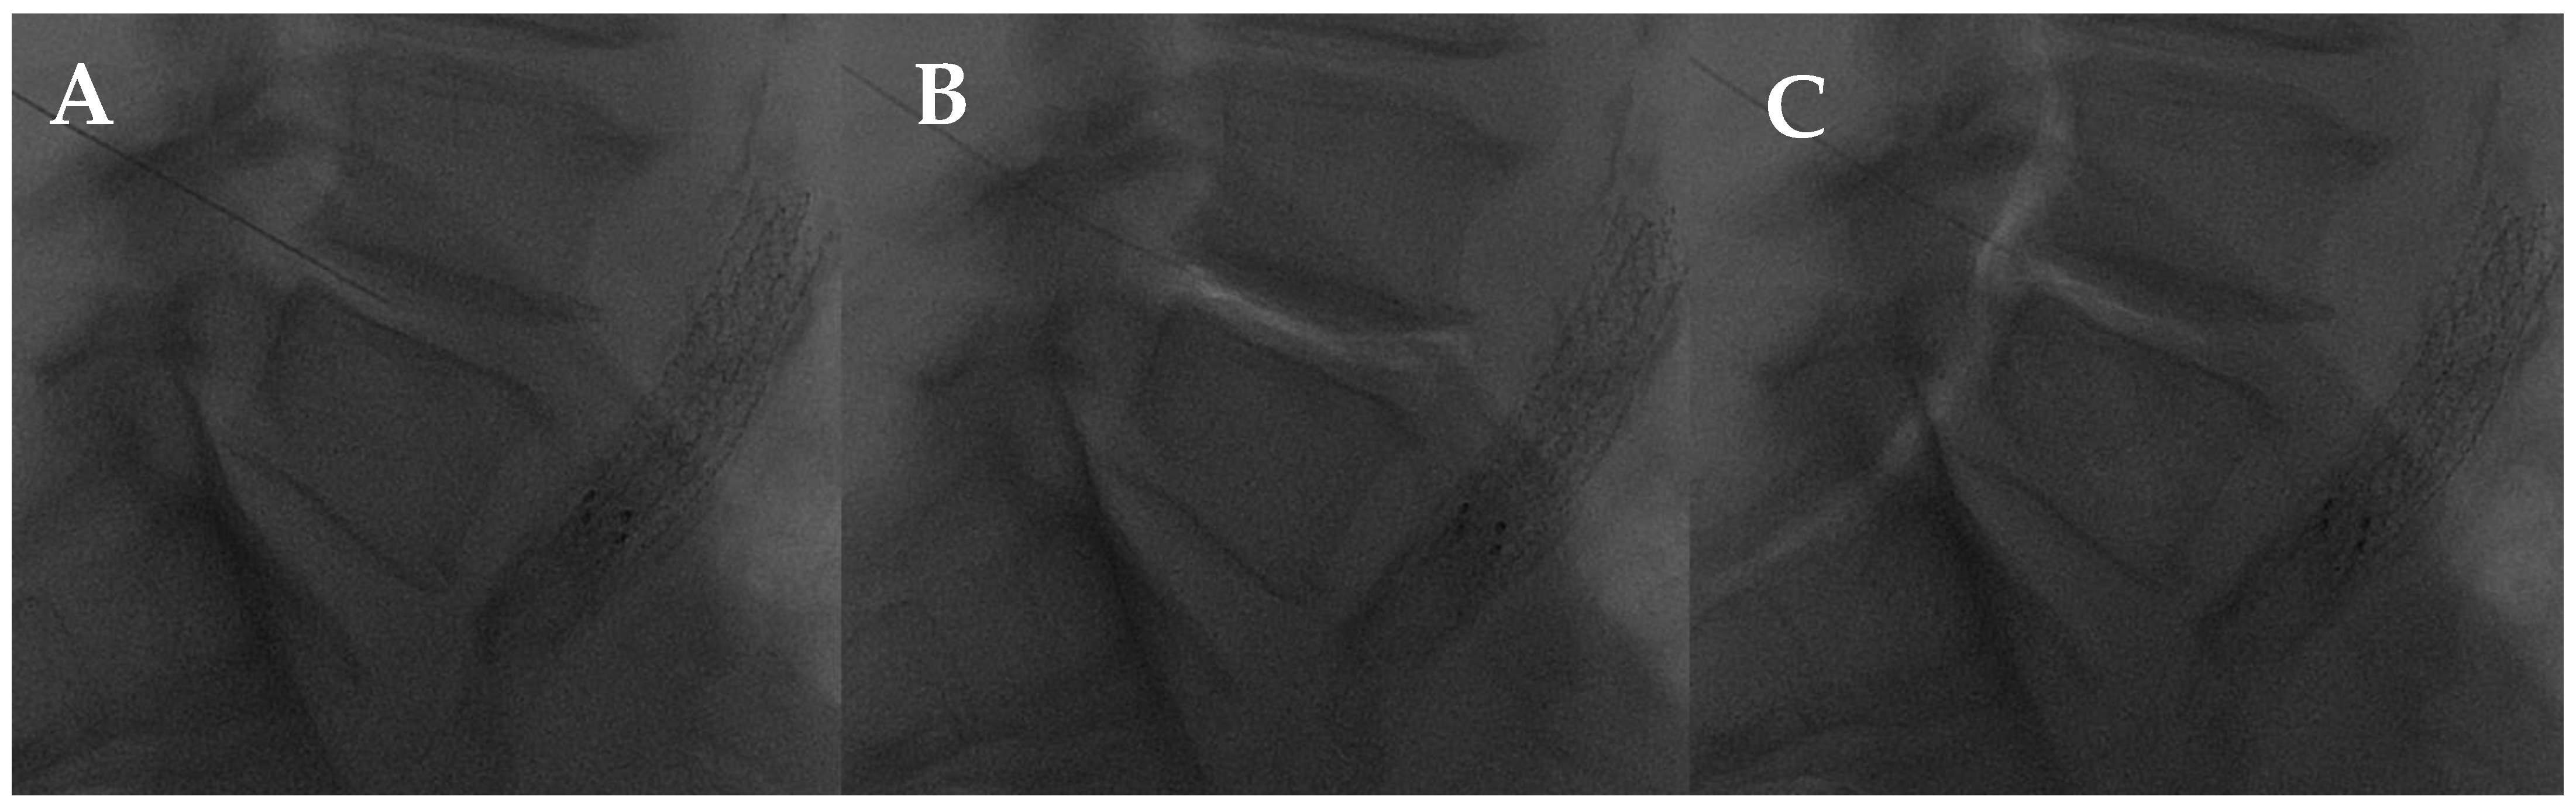

- Marcia, S.; Saba, L.; Anselmetti, G.C.; Marini, S.; Piras, E.; Marras, M.; Masala, S.; Georgy, B. Effectiveness of Percutaneous Screws for Treatment of Degenerative Lumbar Low Back Pain. Cardiovasc. Intervent. Radiol. 2014, 37, 1329–1335. [Google Scholar] [CrossRef] [PubMed]

- Amoretti, N.; Amoretti, M.-E.; Hovorka, I.; Hauger, O.; Boileau, P.; Huwart, L. Percutaneous Facet Screw Fixation of Lumbar Spine with CT and Fluoroscopic Guidance: A Feasibility Study. Radiology 2013, 268, 548–555. [Google Scholar] [CrossRef]